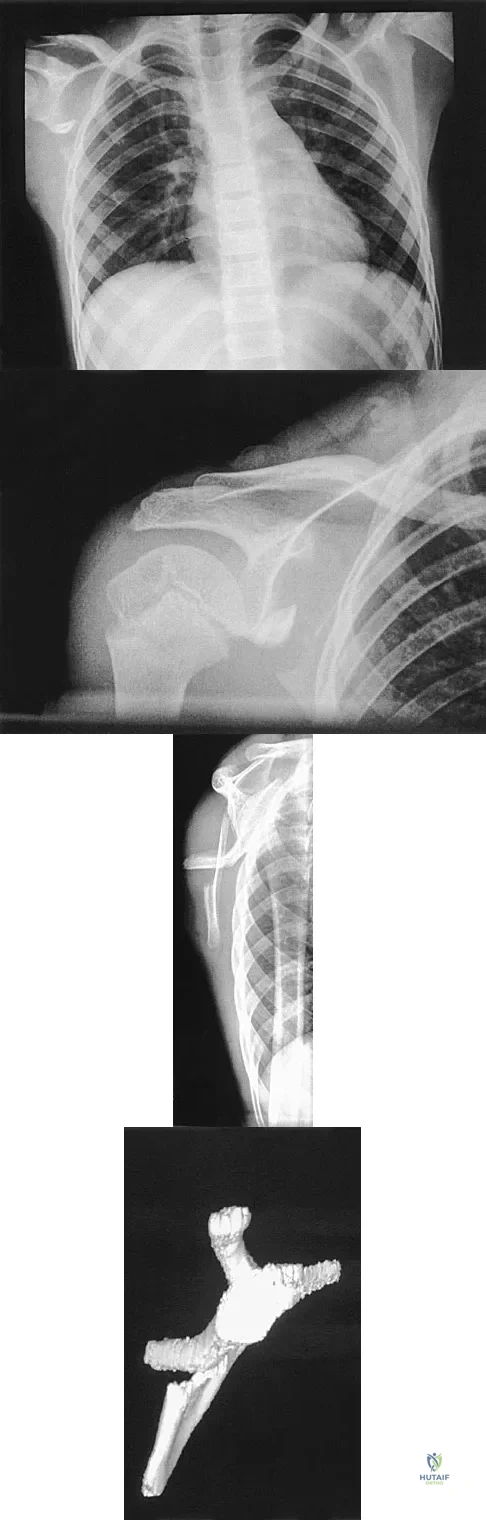

Question 55

A 12-year-old boy has severe left shoulder pain after being struck by an automobile. A chest radiograph, AP and lateral radiographs, and a CT scan with three-dimensional reconstruction of the scapula are shown in Figures 38a through 38d. Management should consist of

Explanation